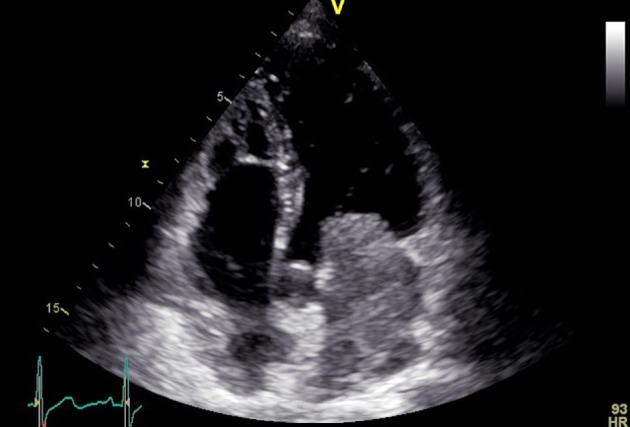

Myxoma is the most common primary cardiac tumor and is usually located in the left atrium. Clinical manifestation relies in large part on the size, location, and architecture of the tumor. There are many reports in the literature of cardiac myxomas causing syncope, embolism, even myocardial infarction. We present a rare case of a patient who underwent urgent surgical resection of a large left atrial myxoma mimicking mitral stenosis. The postoperative course of the patient was uncomplicated. One year after surgery, the patient is asymptomatic and disease-free.

黏液瘤是最常见的原发性心脏肿瘤,通常位于左心房。临床表现很大程度上取决于肿瘤的大小、位置和结构。文献中有许多关于心脏黏液瘤导致晕厥、栓塞甚至心肌梗死的报道。我们报告一例罕见病例,患者因酷似二尖瓣狭窄的巨大左心房黏液瘤接受了紧急手术切除。患者术后过程顺利。术后一年,患者无症状且无疾病复发。